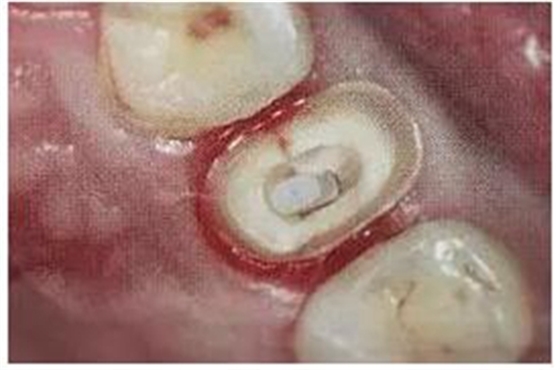

10.毛刷的選用

纖維樁粘接時(shí)應(yīng)使用根管專用的微型毛刷。形態(tài)和樁道吻合,毛刷頭部可彎曲,以達(dá)到較深的根管底端,有利于粘接劑的均勻涂布。

(毛刷運(yùn)用(錯(cuò)誤))

(根管專用毛刷)

采用納米級毛刷,根管涂擦后可較好的提高粘接效果。